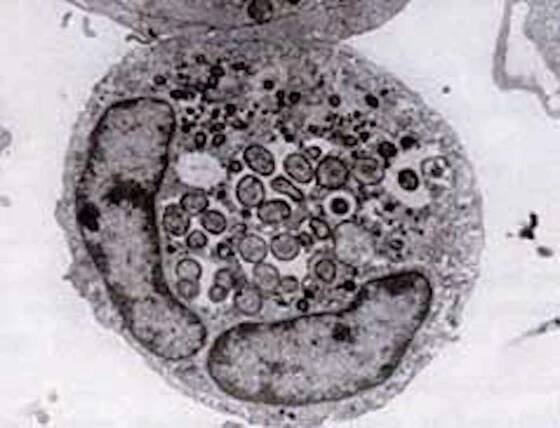

English: This bacterium is transmitted by Ixodes ricinus ticks to deer, sheep and cattle. It specifically infects the neutrophil white cells of the host's blood, causing a suppression of immunity against bacterial infection.

Toto onemocnění je způsobené velice drobnými intracelulárními bakteriemi Anaplasma phagocytophilum patřící do řádu Rickettsiales, které infikují bílé krvinky (neutrofilní granulocyty) hostitele a způsobují závažné onemocnění, nazývané…